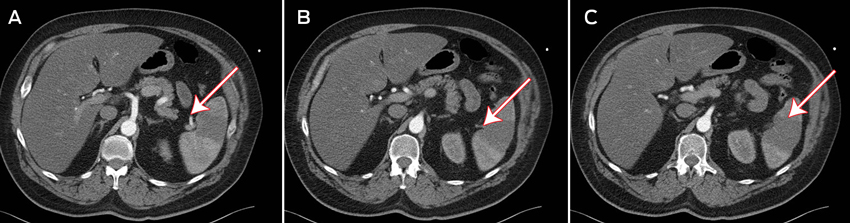

Three days after admission, the patient developed left flank pain with a distended abdomen and guarding in the left upper quadrant. An urgent contrast computed tomography scan showed a wedge-shaped, hypodense area with absent perfusion in the lower pole of the spleen, consistent with an infarction (Figures A–C). A thrombus was identified in a small branch of the splenic artery supplying the lower pole of the spleen (Figure B). No source of the thrombus was found on transthoracic echocardiography (TTE) or transoesophageal echocardiography (TOE), and results of thrombophilia screening were negative. Although the patient received intravenous heparin anticoagulation therapy during this time, his APTT was subtherapeutic (32 s). The infarction was mananged conservatively.

A: Contrast medium entering the inferior branch of the splenic artery, with absent perfusion in the lower pole of the spleen.

B: A visible thrombus in the inferior branch of the splenic artery.

C: Splenic infarction, seen as a wedge-shaped, hypodense area.